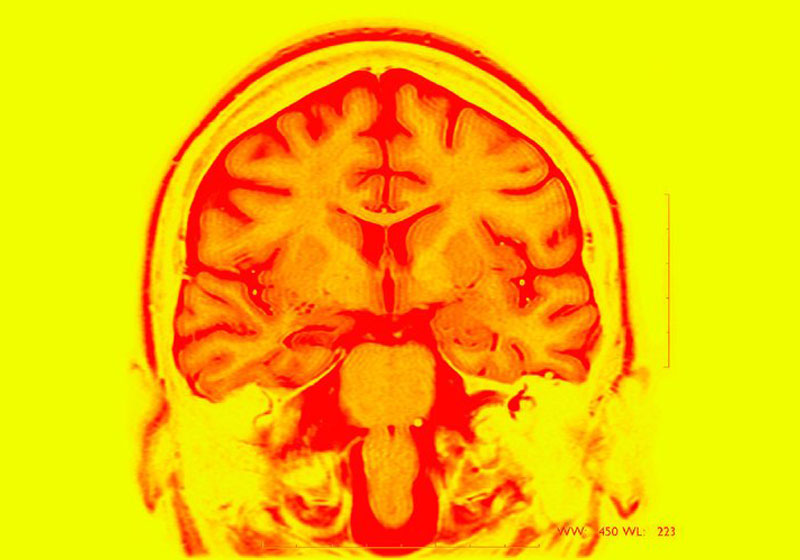

Chega de esquecimento! Cientistas norte-americanos desenvolveram um implante cerebral que aumentou a memória dos voluntários nos primeiros testes, uma nova estratégia promissora para tratar demência, lesões cerebrais traumáticas e outras condições que prejudicam a memória.

O dispositivo envia pulsos elétricos para auxiliar o cérebro quando ele está lutando na tentativa de armazenar novas informações, mas deixa de agir quando percebe que o cérebro está funcionando bem.

O implante baseia-se em anos de trabalho decodificando sinais cerebrais, com apoio de mais de US $ 70 milhões do Departamento de Defesa dos EUA para desenvolver tratamentos para lesões traumáticas do cérebro, a ferida das guerras no Iraque e no Afeganistão.

Os médicos implantaram uma série de eletrodos nas áreas de memória do cérebro.

O implante exige que vários eletrodos sejam colocados no cérebro para determinar seu estado de alto ou baixo funcionamento (embora a estimulação seja enviada para apenas um local).